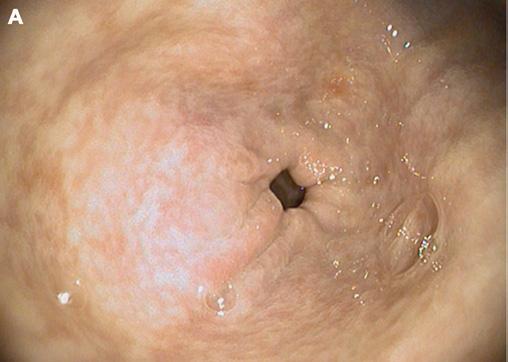

Understanding gastric ulcers

Equine gastric ulcer syndrome (EGUS) is a general term used to describe erosions and ulcers of the horse’s stomach and is similar to the term peptic ulcer disease in people. Unlike people however, the horse is unique in that the stomach lining (mucosa) is divided into an upper squamous and a lower glandular portion (Fig. 1); and it is important to realise that there are differences between these two regions with respect to how these lesions develop, their prevalence, associated risk factors and response to treatment. Therefore, when referring to EGUS, your vet may use the terms equine squamous gastric disease (ESGD) and equine glandular gastric disease (EGGD) to clearly distinguish the anatomical region of the stomach affected.

There does not appear to be a clear relationship between the presence of squamous disease and glandular disease, and the fact that both conditions may occur concurrently in the same horse does not indicate that they are associated. In the case of squamous disease, the cause of the ulcers is well understood, with a variety of managemental risk factors (e.g. increase in exercise intensity, low roughage/high starch diet, stall confinement) contributing to an

increase in the exposure of the squamous mucosa to acid. The squamous mucosa is not normally exposed to acid. As such, it is inherently susceptible to acid injury, and with prolonged acid exposure, ulcers may develop (Fig. 2).

In contrast to squamous disease, the cause of glandular disease is poorly understood. The glandular mucosa is fundamentally different from the squamous mucosa in that it is exposed to a highly acidic environment under normal physiological conditions. As such, it is only when there is a breakdown of the normal defence mechanisms that protect the glandular mucosa from acidic gastric contents that glandular disease occurs. While ulcers are most commonly seen with squamous disease, horses with glandular disease rarely present with ulcers. Rather, the lesions are more consistent with an erosive inflammatory gastritis and can vary widely in their appearance (Fig. 3).

1

LEFT: A normal equine stomach with squamous mucosa (white) and glandular mucosa (pink). FIG BELOW: Normal squamous mucosa (A) and ulcers (arrow) in the squamous mucosa of a horse with equine squamous gastric disease (ESGD) (B). FIG 2